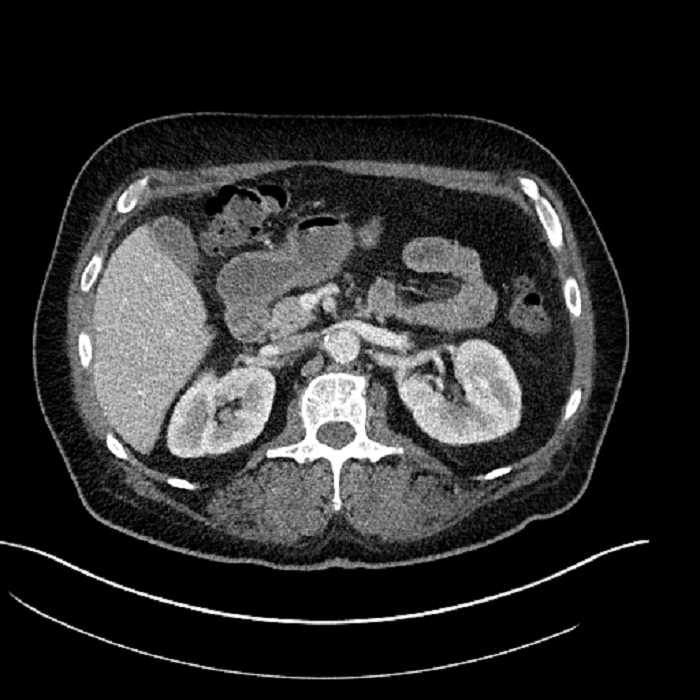

• Large fluid density structure in hepatic segments 7 and 8 measuring 10 x 7 x 7 cm with internal septation and circumferential ill-defined low density compatible with edema

• Peripherally enhancing subcapsular collections along the anterior margin of the left hepatic lobe measuring 3 x 1 cm and 2 x 1 cm

• Clearly marginated fluid density structure in segment 7 and several other scattered tiny hypodensities, which likely represent cysts

Acute sigmoid diverticulitis complicated by a small contained perforation and a large abscess in the right hepatic lobe. Additional small subcapsular abscesses along the anterior margin of the left hepatic lobe.

• The classic CT imaging appearance is a double target sign with internal low density surrounded by an internal enhancing rim (capsule) and a low density external rim (edema)

Hepatic abscess showing the double target sign with low density internally surrounded by a thin inner enhancing rim (red arrow) and ill-defined outer low density rim (yellow arrow). Blue arrow indicates an internal septation. Red arrows: additional smaller subcapsular abscesses. Red arrow: focal contained perforation associated with diverticulitis.